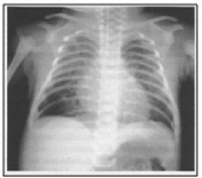

A Figura 1 é uma imagem radiológica de um quadro clássico de síndrome de aspiração de mecônio. Observe-a com atenção e assinale a alternativa correta:

Figura 1: Imagem radiológica de síndrome de aspiração de mecônio.

Fonte: SARMENTO, G. J. V. Fisioterapia respiratória no paciente crítico. Barueri: Manole, 2005. p. 450.